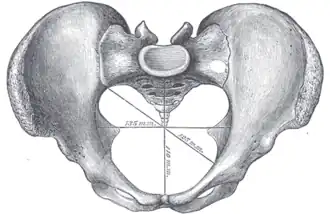

Diameters

The diameters or conjugates of the pelvis are measured at the pelvic inlet and outlet and as oblique diameters.

| Name | Description | Average measurement in female |

|---|---|---|

| Anteroposterior or conjugate diameter or conjugata vera | Extends from the upper margin of the pubic symphysis to the sacrococcygeal joint; | about 110 mm. |

| Transverse diameter | Extends across the greatest width of the superior aperture, from the middle of the brim on one side to the same point on the opposite; | about 135 mm. |

| Oblique diameter | Extends from the iliopectineal eminence of one side to the sacroiliac articulation of the opposite side; | about 125 mm. |

| Anatomical conjugate | Extends from the pubic symphysis to the promontory; | about 120 mm. |

| Diagonal conjugate | Extends from lower margin of the pubic symphysis to the sacral promontory; | about 130 mm. |

| Straight conjugate | Extends from the lower border of the pubic symphysis to the tip of coccyx. The coccyx can bend posteriorly and expand the diameter with 25 mm; | about 95 mm (+ 25 mm). |

| Median conjugate | Extends from the lower border of the pubic symphysis to the lower border of the sacrum; | about 115 mm. |

Obstetric conjugate, as a measure of the pelvic inlet in the sagittal plane